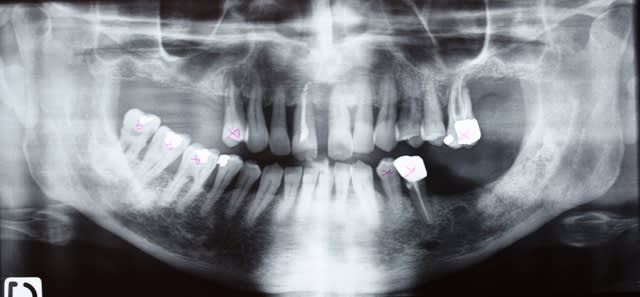

Allez trois autre photos

Ne me dites que les dents restantes à la mandibule sont pourries sur le plan paro... Je le sais

Prochainement étape : virer les molaires avec PRFs et poser déjà deux implants en 35 45 en enfoui...et qd les PRFs auront fait leur oeuvre : implanto totale du bas